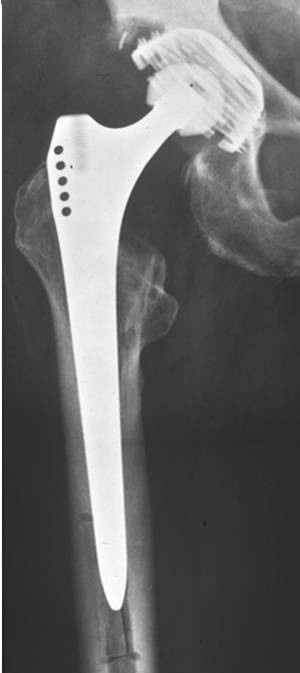

Standardschäfte oder Monoblock-Revisionsschäfte erlauben in nur sehr begrenztem Umfang die Adaptation an diese Bedingungen. Sie erfordern in der Regel eine distale Fixierung, ermöglichen nur eine inkomplette Füllung der Defekte, Offset und Anteversion sind nicht variabel und die Beinlängenadaptation limitiert (Abb. 1a, b).